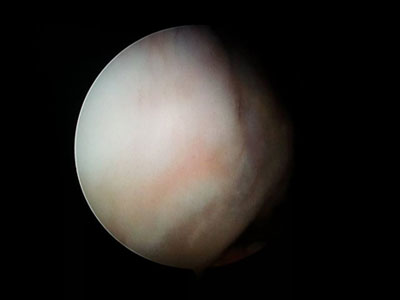

Arthroscopy

Minimally invasive “keyhole” surgery for diagnosing and treating joint issues like torn ligaments or cartilage in knees and shoulders.

Performed by Dr Naveen Palla, this approach helps reduce pain and ensures faster recovery with smaller incisions